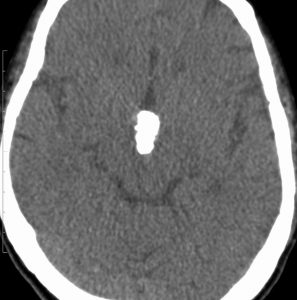

1968年 18歳の時に頭痛嘔吐で発症しました。第3脳室腫瘍と閉塞性水頭症の診断だけで,シャント手術を受けました。手術も化学療法も放射線治療もされていません。下の画像は60代で撮影されたものです。この例では,第3脳室内に増大した大きな毛様細胞性星細胞腫が,視床下部下垂体障害を出すことなく,自然経過で増大停止 growth arrest して,カチカチに固まってしまうということを教えてくれます。でも,こんなに都合よく経過観察できる例も珍しいです。

CTでは強い石灰化があります。右のT2強調画像では腫瘍は等信号,視交叉の後ろにあります。内部の低信号は石灰化です。